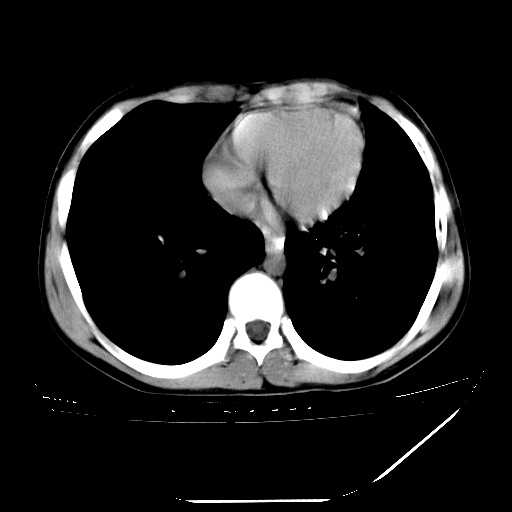

男,13岁,咳嗽、咳痰伴发热一周。

中上纵隔见多枚淋巴结肿大,部分相互融合成团片,左肺门增大,上叶支气管变窄,肺内多处斑片状 索条状及棉絮状致密影。临床“男,13岁,咳嗽、咳痰伴发热一周。”首先考虑:原发综合征!不除外淋巴瘤可能!

纵隔多发肿大淋巴结,部份有融合改变。双肺血管气管束增厚,以肺门为中心向外周散发,以左肺下叶为明显。考虑淋巴瘤可能性大。不除外原发综合征。

中上纵隔见多枚淋巴结肿大,部分相互融合成团片,左肺门增大,上叶支气管变窄,左肺支气管血管束增粗,可见磨玻璃样影。临床“男,13岁,咳嗽、咳痰伴发热一周。”首先考虑:淋巴瘤可能性大!

中上纵隔见多枚淋巴结肿大,部分相互融合成团片,纵隔内脂肪间隙模糊,左肺门增大,上叶支气管变窄,左肺支气管血管束增粗,可见磨玻璃样影。考虑纵隔淋巴管炎